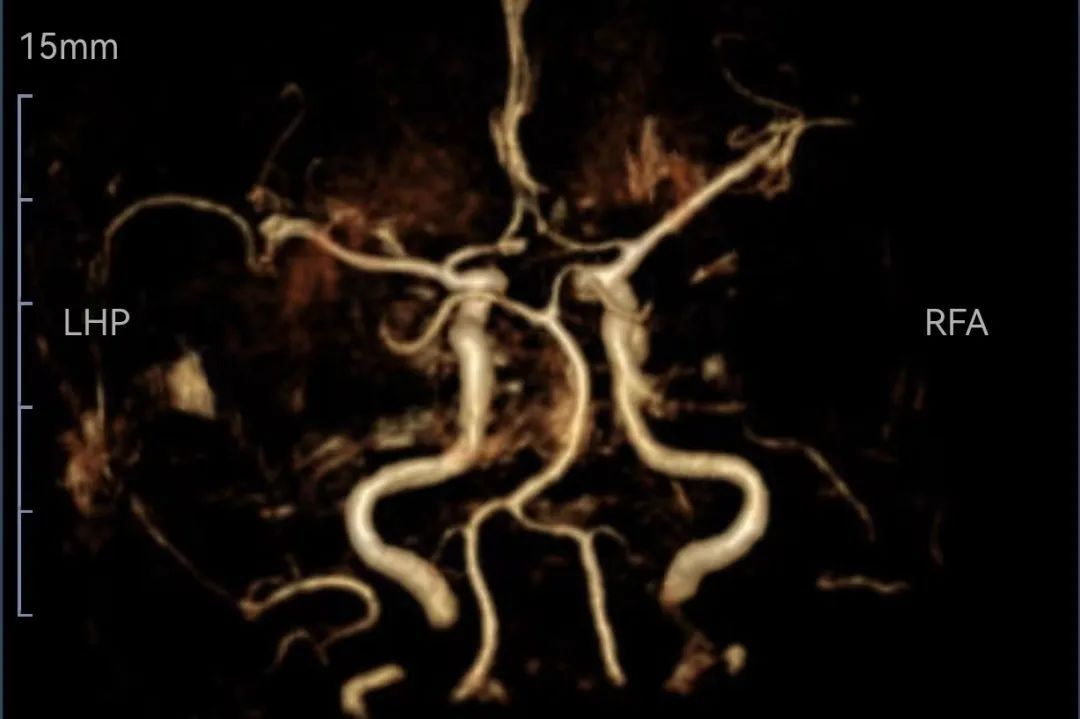

溶栓后头颅磁共振MRA血管畅通

溶栓后患者在医生及护士陪同下前往影像中心检查头颅磁共振,等候磁共振检查时再次评估,患者右侧肢体可抬离床面;NIHSS评分7分(意识2,面瘫1、右下肢运动2、感觉1、语言1),查头颅磁共振示:左侧额、顶、颞、枕叶急性脑梗塞;头颅磁共振MRA颅内大血管未见明显异常,随后收入神经内科给予进一步治疗。